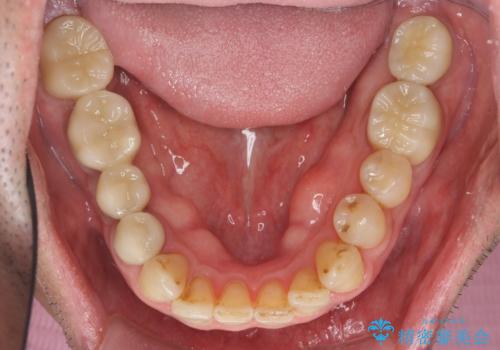

インプラント治療・セラミック治療を含む 全顎的虫歯治療

- 「 仕事が忙しく、虫歯を放置しすぎてしまった。この際全てきっちりと治したい。」と来院されました。

・歯の欠損

・虫歯

・深い虫歯

・欠損の放置による対合歯の挺出

・咬合平面の乱れ

・感染根管

以上のような問題を、徹底的な虫歯治療、歯周外科、インプラント治療、部分矯正治療、精密根管治療を用いてひとつずつ解決ししっかりと長期的に食事を楽しめるような口腔内環境の再構築を目指します。